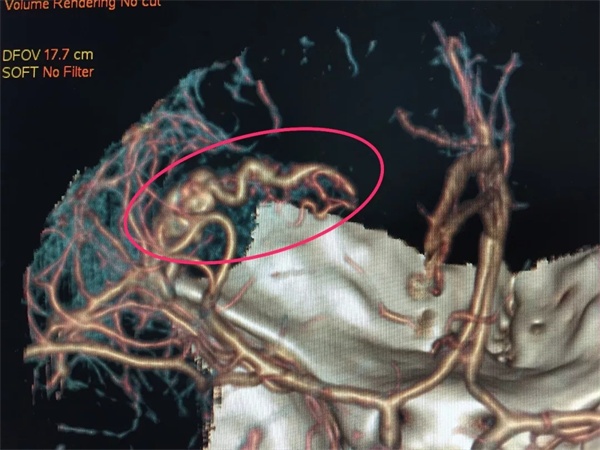

2018年12月1日上午11时30分,家住红谷滩新区的18岁美少女佳佳在坐车回家途中,突然出现剧烈头痛,继而陷入昏迷,旁边的朋友紧急呼叫120把她送入捕鱼游戏 。 入院查体: 体温:36.5°,脉搏80次/分,呼吸20次/分,血压:121/69mmHg。双肺呼吸音清晰,未闻及干湿性罗音; 神经系统检查:神志嗜睡,呼唤睁眼,语言清晰,对答基本切题,双侧瞳孔等大等圆,直径3.0mm,光反应存在,眼球活动度好,鼻唇沟不变浅,伸舌居中,咽反射存在,转颈,耸肩好。颈软,克氏征阴性。四肢肌力肌张力正常,双侧感觉检查无异常,双侧腱反射对称,双侧病理征未引出,双侧指鼻试验、跟膝胫试验完成可。 急诊头颅CT:左侧额叶出血,左侧急性硬脑膜下血肿,左侧外侧裂池积血。

手术目前是脑血管畸形最主要也是最有效的治疗手段。由于脑动静脉畸形的血管发育异常,手术出血凶险、止血困难,对神经外科医生手术技术和多学科团队配合要求高。目前捕鱼游戏 影像科设备齐全,图像质量好,诊断水平高,对脑动静脉畸形的确诊率在95%以上,神经外科手术团队和介入团队针对脑动静脉畸形已全面开展显微手术切除和介入栓塞工作。